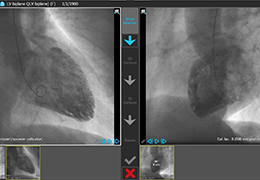

ANYTHINK 经导管主动脉瓣膜置换术分析系统